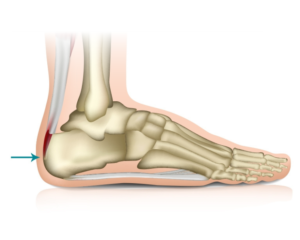

La Enfermedad de Sever o apófisis calcánea es una causa frecuente de dolor en el talón infantil. Suele aparecer entre los 7 y los 12 años de edad y es más frecuente en el género masculino y en aquellos niños que realizan actividad deportiva.

La apófisis calcánea es una inflamación aguda del cartílago por el desarrollo del talón. Durante el periodo de crecimiento se genera tensión muscular en el Tendón de Aquiles y la fascia del pie.

Al tratarse de una patología provocada por la tracción excesiva y repetida del Tendón de Aquiles, el tratamiento irá encaminado a disminuir esa tensión.